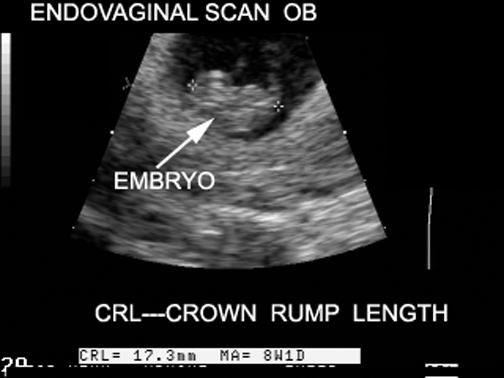

Crown Rump Length (CRL) |